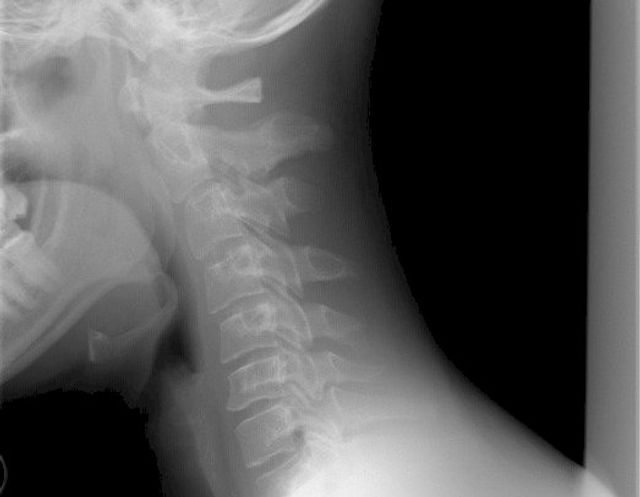

В екатеринбургской гимназии №99 дети сломали позвоночник однокласснику. По предварительной информации, инцидент произошел на уроке физкультуры в шестом классе.